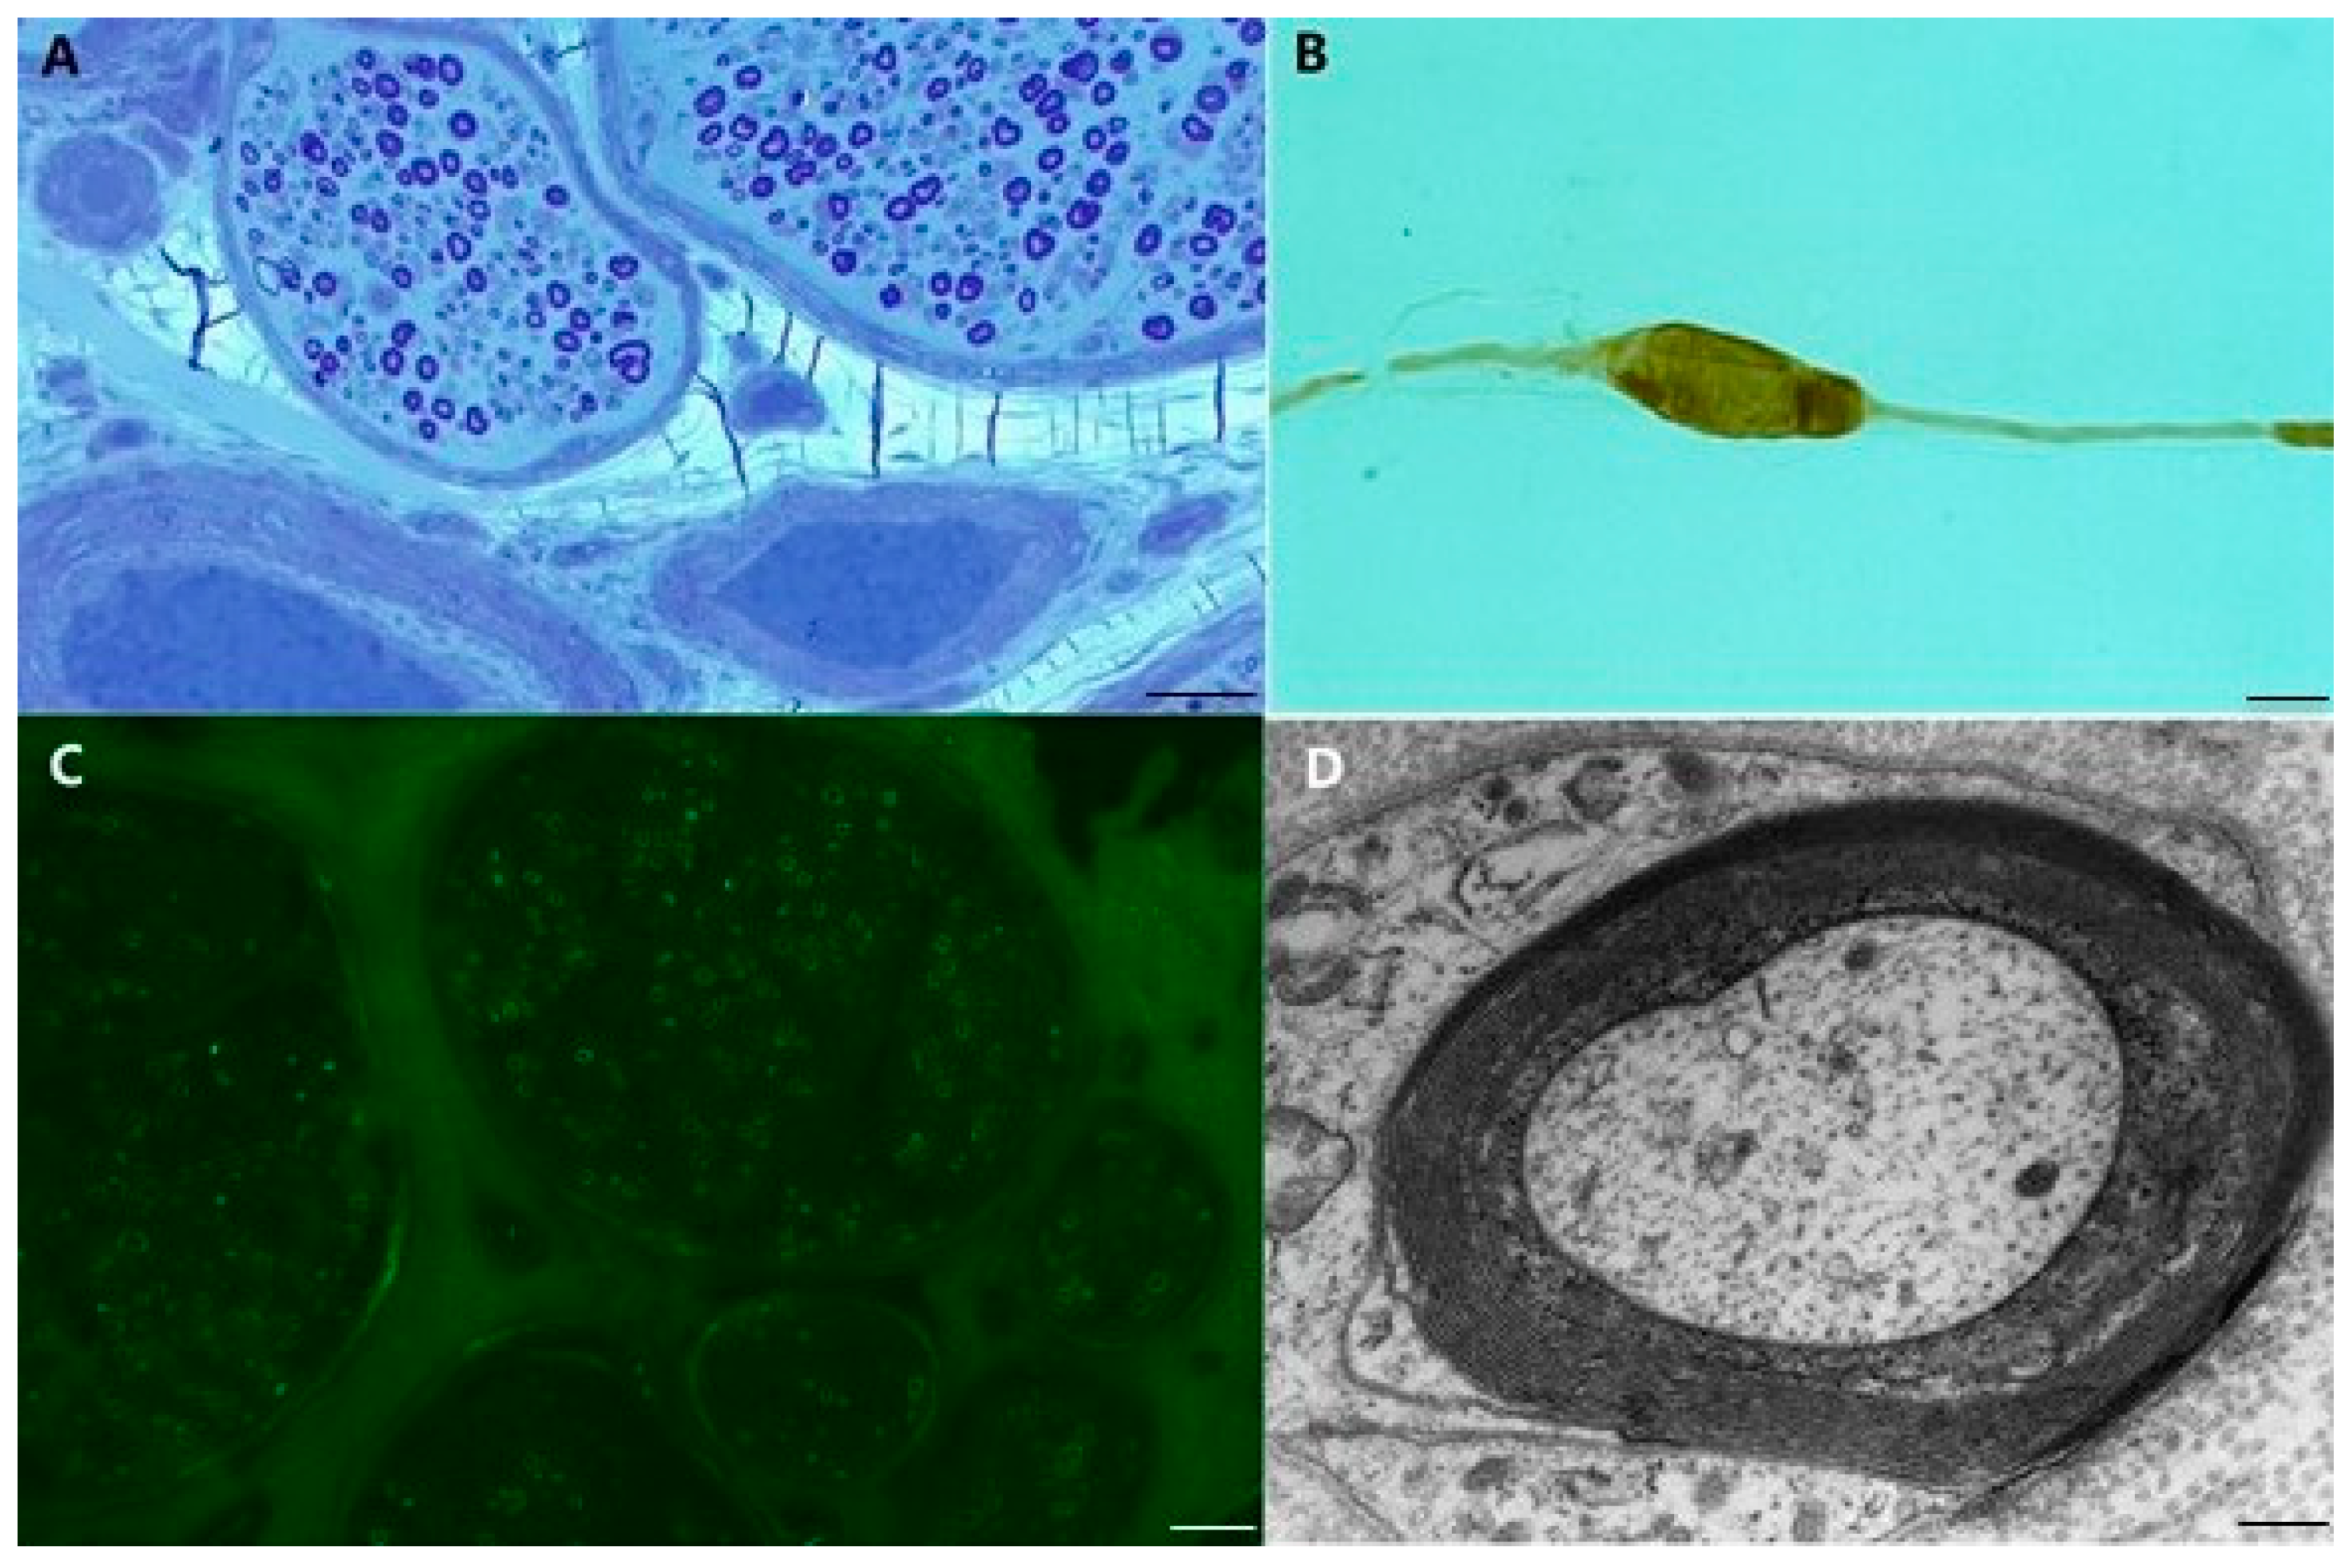

Mechanisms of Nerve Damage in Neuropathies Associated with